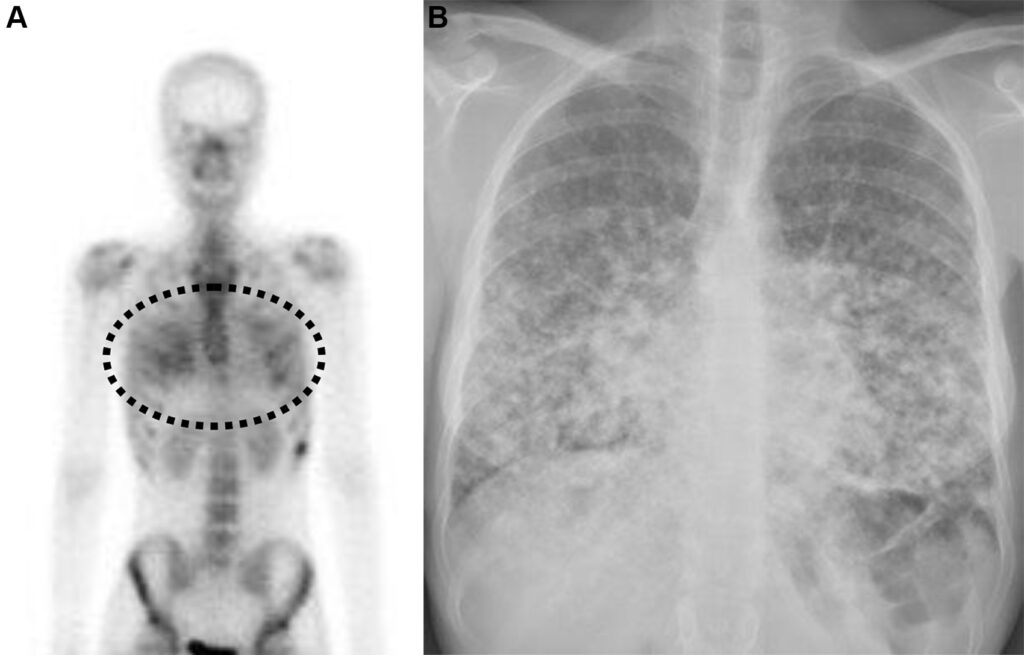

Malattia metastatica con pattern miliare in una donna di 44 anni con carcinoma papillare della tiroide.

L’esame total body rileva una tenue ipercaptazione diffusa e simmetrica a livello di entrambi i campi polmonari. Si tratta di una captazione extra-ossea anomala del radiotracciante osteotropo. L’imaging morfologico dell’Rx conferma la presenza di una massiva disseminazione metastatica polmonare, caratterizzata da innumerevoli e minuscoli noduli bilaterali (il classico “pattern miliare”), più addensati alle basi. Il tecnezio difosfonato (99mTc-MDP) può accumularsi in lesioni metastatiche extra-ossee, come quelle polmonari derivanti da alcuni tumori (tra cui il carcinoma tiroideo, mammario o osteosarcoma). Questo fenomeno è spesso dovuto alla presenza di microcalcificazioni all’interno del tessuto neoplastico o ad alterazioni del metabolismo locale del calcio.